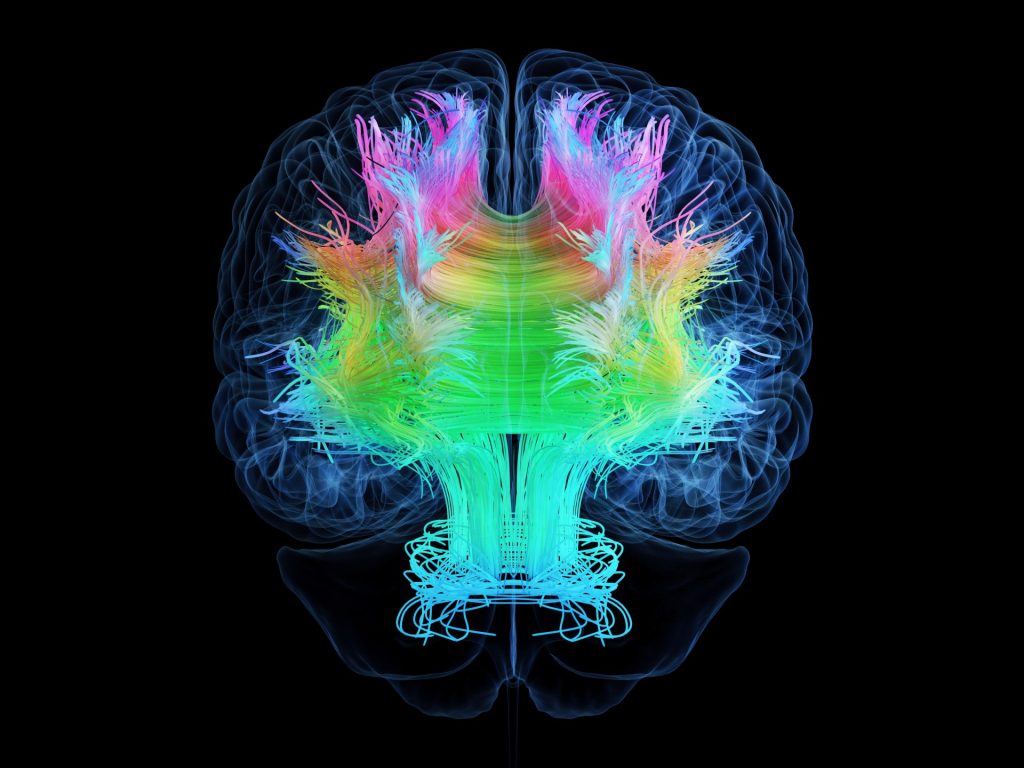

ويشير مصطلح “ضجيج خلفية الدماغ” عادة إلى النشاط العصبي الفطري أو الداخلي الذي يحدث في الدماغ حتى في غياب المحفزات الخارجية، وغالبا ما يكون قياس هذا النشاط العصبي المستمر باستخدام تقنيات مثل تخطيط كهربية الدماغ أو التصوير بالرنين المغناطيسي الوظيفي.

واستخدم الباحثون في عملهم تقنية تخطيط كهربية الدماغ لفحص نشاط الدماغ لدى المرضى الذين يخضعون للعلاج بالصدمات الكهربائية لعلاج الاكتئاب، كما قاموا بالتحقيق في علاج مماثل يسمى علاج النوبات المغناطيسية والذي يحفز النوبات باستخدام المغناطيس بدلا من الأقطاب الكهربائية. وقد أدى كلا العلاجين إلى زيادة مستويات النشاط غير الدوري في أدمغة المرضى بعد العلاج.